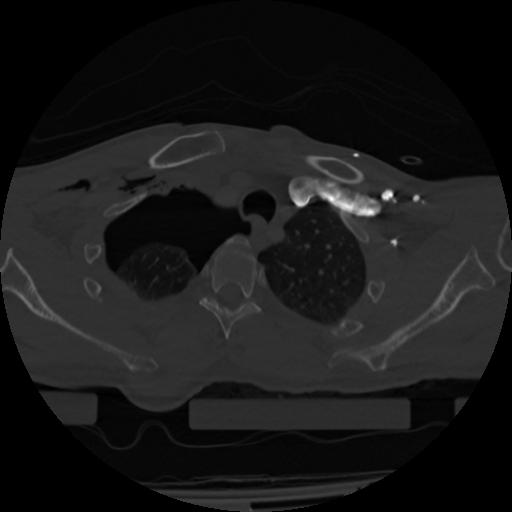

22 ANGIO,CE,Vol,0.5,ANGIO,,